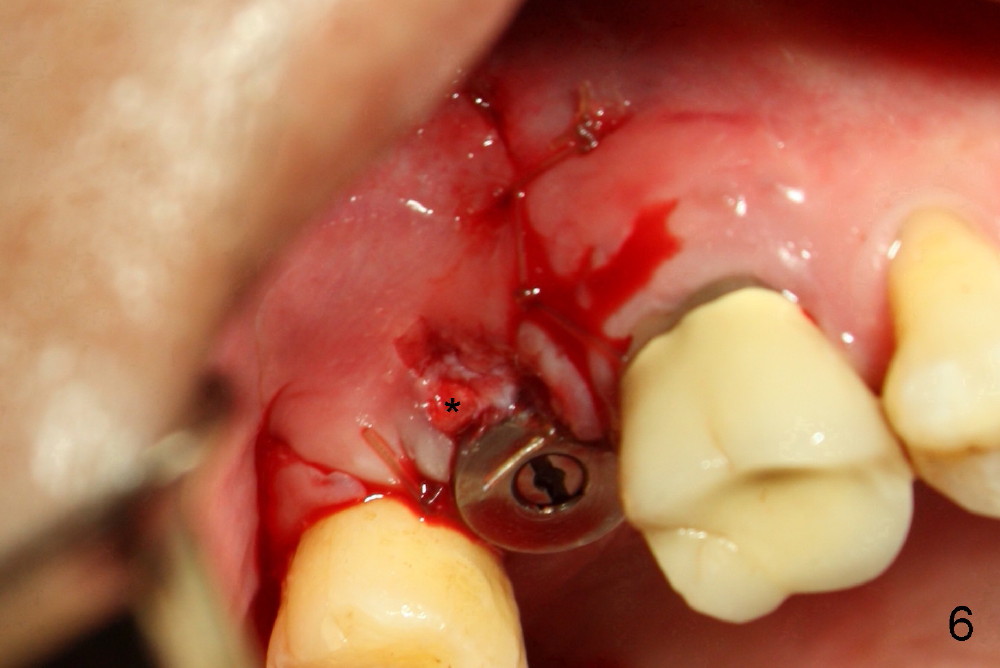

The 60-year-old man is a bruxer. All of the three upper right molars are nonsalvageable (Fig.1). Since #2 is symptomatic, it is planned to be extracted and restored first. As expected, there is severe alveolar destruction (single large socket), while the base bone is solid. A series of tapered osteotomes (2-5 mm) are used to create osteotomy in the base bone (gaining 4 mm into new bone), followed by 4.5x20 mm tap at the depth of 17 mm from the gingival margin (Fig.2). Then the depth is adjusted to 14 mm; the bone expansion and osteotomy continue until using 7 mm tap with good binding to the bone (Fig.3). A 7x14 mm implant is placed with insertion torque more than 60 Ncm (Fig.4). No bone graft is used for sinus lift considering sinus membrane perforation. The buccal flap is raised to reveal bony defect, which is covered by Osteogen (a synthetic bone graft) and then collagen membrane (Fig.6 *). Five days postop, the membrane undergoes a type of transformation (Fig.7 *) leading to a gingival tissue (Fig.8 *, 18 days postop). By 3 months, the gingiva has normal appearance (Fig.9), while the implant seems to be osteointegrated (Fig.10). Once the infected source is removed, our body has potential to regenerate.